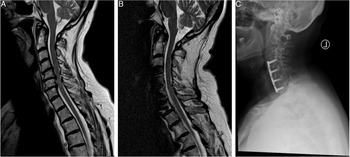

Given the raised concerns for cervical myelopathy, she was sent for an urgent MRI of the cervical spine. Mid-Sagittal T2 images (Figure 2A) revealed multilevel degenerative changes of the IVDs with significant compression of the cord at the C4/5, C5/6 and C6/7 levels with T2-hyperintense myelopathic signal changes. Given her MRI findings and her clinical presentation, she was diagnosed with a mJOA 12 cervical myelopathy. This patient was offered a 3-level ACDF which was done successfully. At 1-year follow-up, the patient was no longer reporting any pain, paresthesia or difficulties with hand motor function but was noted to have continued gait disturbance. Her post-operative mJOA was 16. A postoperative mid-sagittal T2 MRI scan shows a sufficiently decompressed spinal cord (Figure 2B), while the radiograph at follow-up shows an intact anterior plate and evidence of osseous fusion, (Figure 2C).

Figure 2: Illustrative case of a 62-year-old female patient with the diagnosis of a Degenerative Cervical Myelopathy. (A) The preoperative T2-sagittal magnetic resonance imaging shows a multi-level degenerative disc disease at the level of C4/5, C5/6 and C6/7 causing spinal cord compression and myelopathic signal alterations of the cervical spinal cord. Her preoperative mJOA score was 12. (B) The postoperative sagittal T2-MRI at follow-up shows a decompressed spinal cord and reduced myelopathic signals. (C) The postoperative radiograph at 1-year follow-up shows an intact ventral plate and signs of osseous fusion. On follow-up, the patient improved to an mJOA of 16.